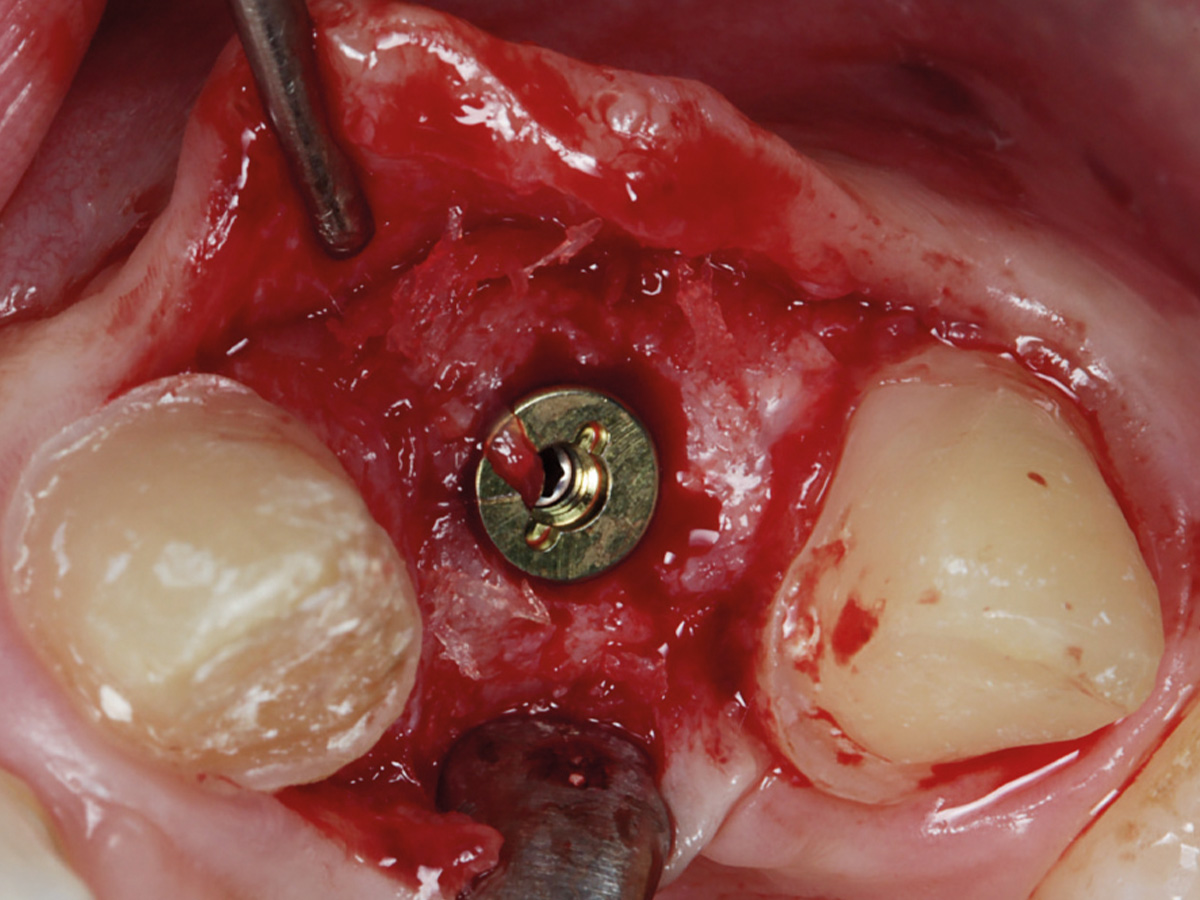

Abbildung 11

Ein Implantat mit 3,8 mm (Ø) konnte in seiner korrekten dreidimensionalen Position eingebracht werden.